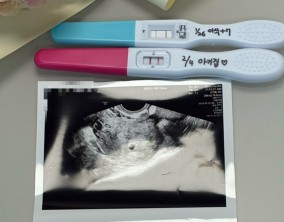

내가 이 병원을 잘 선택한 걸까? 임신으로 답하다

처음에는 하도 유명하다는 병원들이 많아서 “내가 이 병원을 잘 선택한 걸까?”라는 고민이 있었지만, 인공수정과 시험관 시술을 거치면서 이유정 원장님, 간호사 선생님, 직원분…